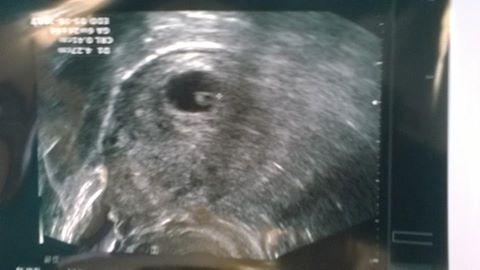

Dnes konečne kontrola, folikuly vpravo do 7mm, vlevo bez tekutiny...na UTZ nic, ale pro jistotu jdu zitra na krev a v pondeli pujdu na vyvolavacku. Myslíte si, ze je to OK nebo neco spatne? Dr se se mnou vubec nebavil, jen mi rekl, ze zatim těhotná nejspíš nejsem a ze se uvidime pristi tyden.